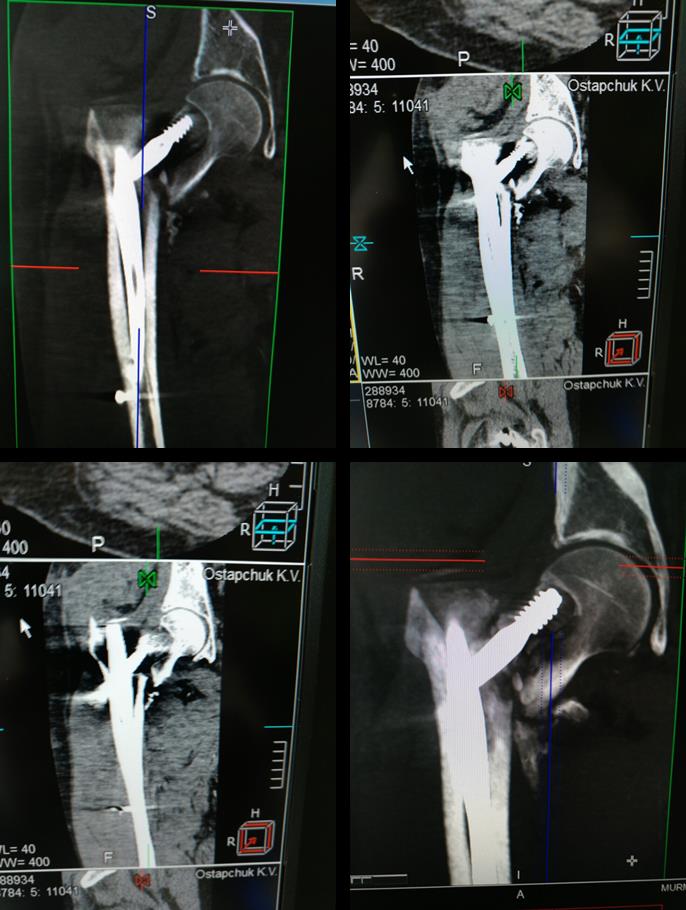

провели предоперационную компьютерную томографию

результат таков

Стало, конечно, лучше, но... Длина не восстановлена, плотного контакта нет. Так что я бы не сильно рассчитывал на благоприятный исход. И на всякий случай уже сейчас думал, что делать в случае cut out.

Особенно не внушает уверенности в конечном успехе то, что видим на аксиальном снимке